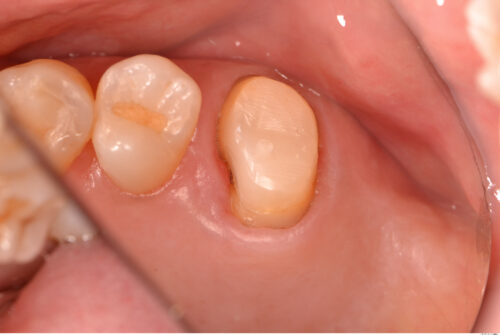

保険適用のチタンクラウンで修復しました。

根管内を緊密に根管充填されていることが分かります。またチタンクラウンはエックス線に対して半透過性があるのも特徴です。